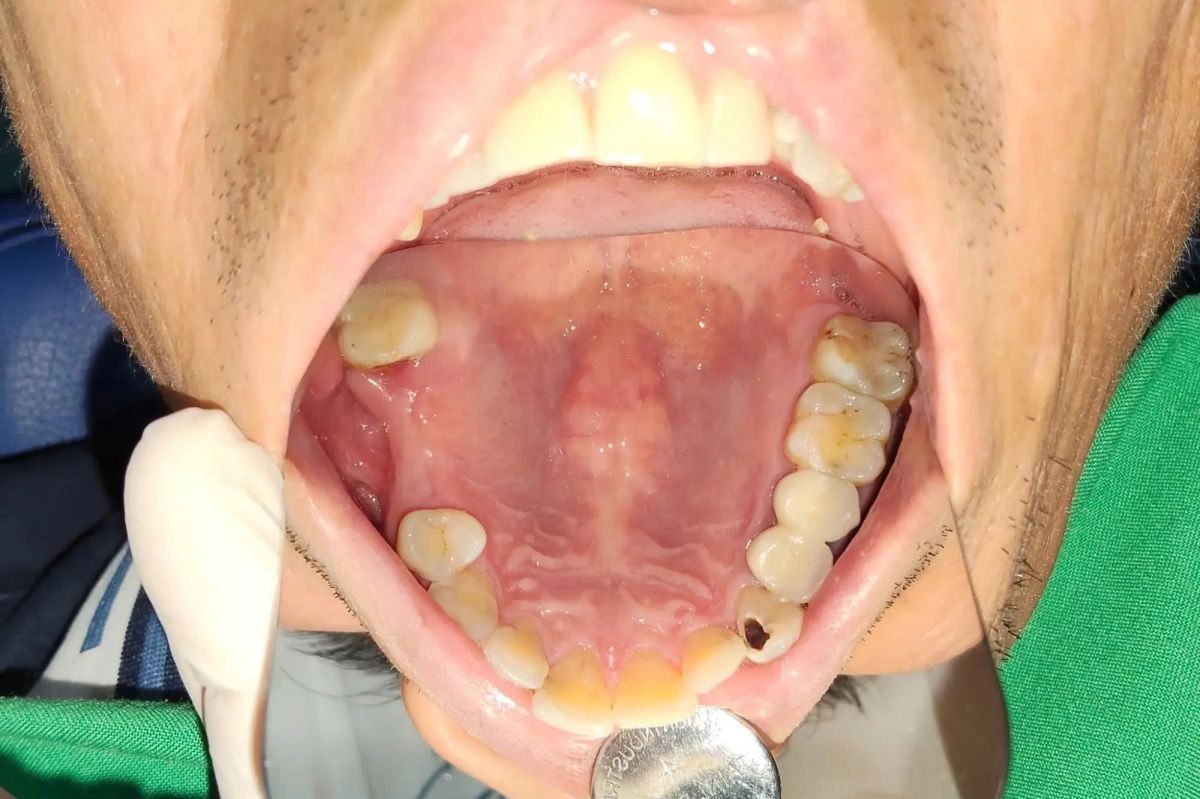

Tình trạng ban đầu

Khi đến thăm khám tại nha khoa, anh Quang được chẩn đoán:

- Mất răng R15, R16 (vùng răng hàm trên)

- Khoảng mất răng kéo dài khiến lực nhai giảm, thức ăn dễ giắt vào khoảng trống

- Nguy cơ tiêu xương hàm nếu không can thiệp kịp thời

Việc thiếu răng hàm không chỉ gây bất tiện khi ăn nhai mà còn ảnh hưởng đến các răng kế cận, lâu dài có thể dẫn đến sai khớp cắn và suy giảm chất lượng sống.